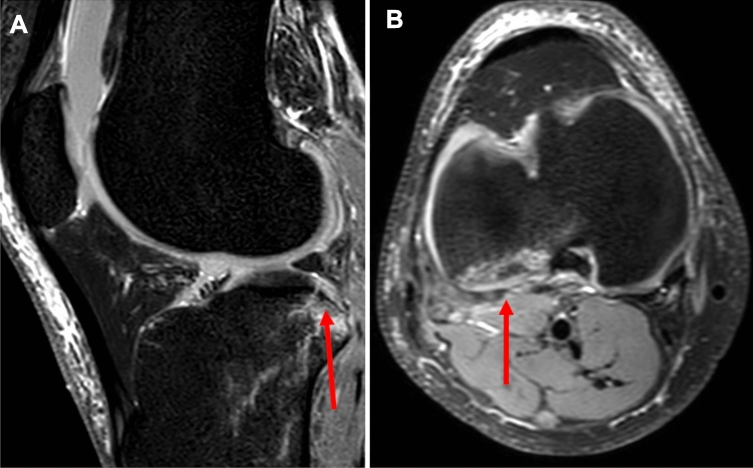

Fig. 3.

Illustration of an MRI of a left knee joint in A saggital section plane showing a posterolateral fracture of the tibial plateau (arrow) and B transversal section plane showing a posterolateral fracture of the tibial plasteau